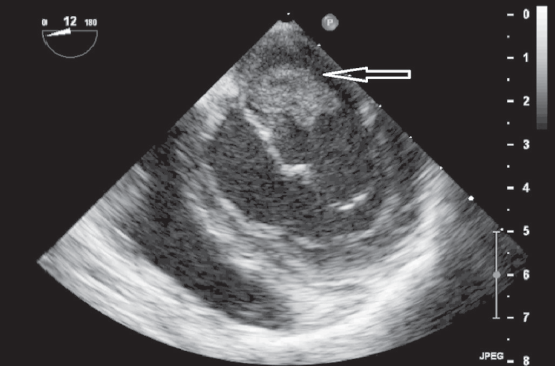

Чреспищеводная ЭхоКГ: визуализирована большая вегетация, длиной более 1 см, фиксированная своим основанием к задней сворке МК и вегетации на передней створке МК (рис. 5, 6).

Рис. 5. Чреспищеводная эхокардиограмма пациентки А., 16 лет. Продольная ось сердца. Стрелками указаны вегетации на задней створке митрального клапана

Fig. 5. Transesophageal ECHO of 16-year old female patient A. Long axis. Arrows indicate vegetations on the mural leaflet of the mitral valve

Рис. 6. Чреспищеводная эхокардиограмма пациентки А., 16 лет. Поперечная ось сердца. Стрелками указаны вегетации на задней створке митрального клапана

Fig. 6. Transesophageal ECHO of 16-year old female patient A. Short axis. Arrows indicate vegetations on the mural leaflet of the mitral valve